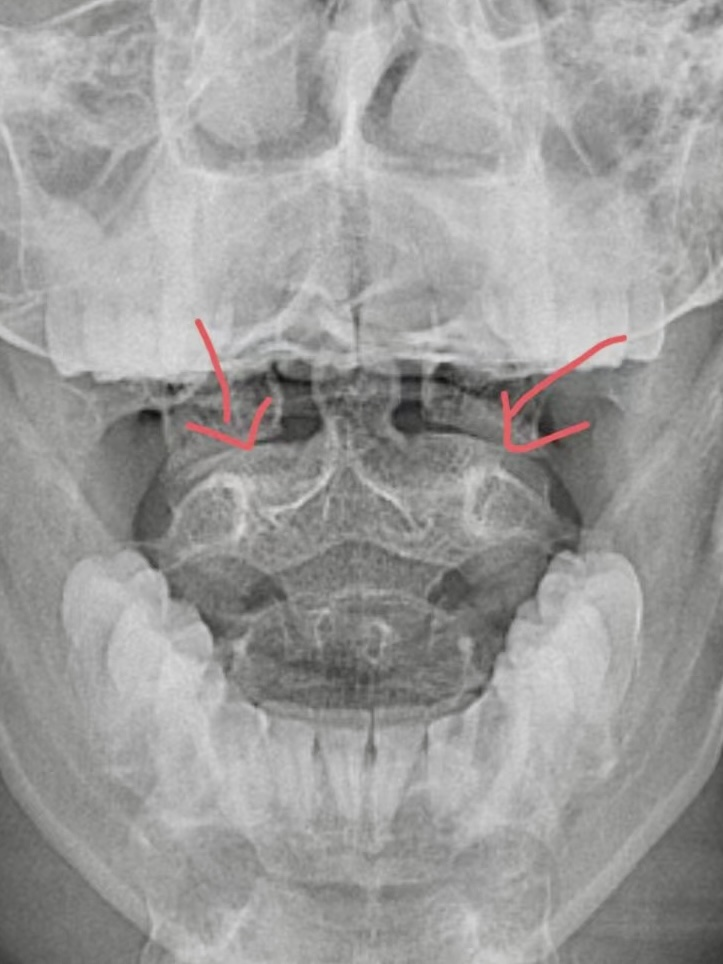

通常X线片可帮助诊断。张口位X线片可见枢椎齿突与寰椎两侧块的间距不对称。侧位X线片能够清楚显示齿突和寰椎前弓之间的距离变化,正常情况下在3mm以内。

图片

对于儿童,由于摄片时合作不好,经常不能满意显示该区域解剖结构,可能需多次反复拍摄。通常建议直接行颈椎CT平扫+三维重建检查,更加明确寰枢椎位置情况。